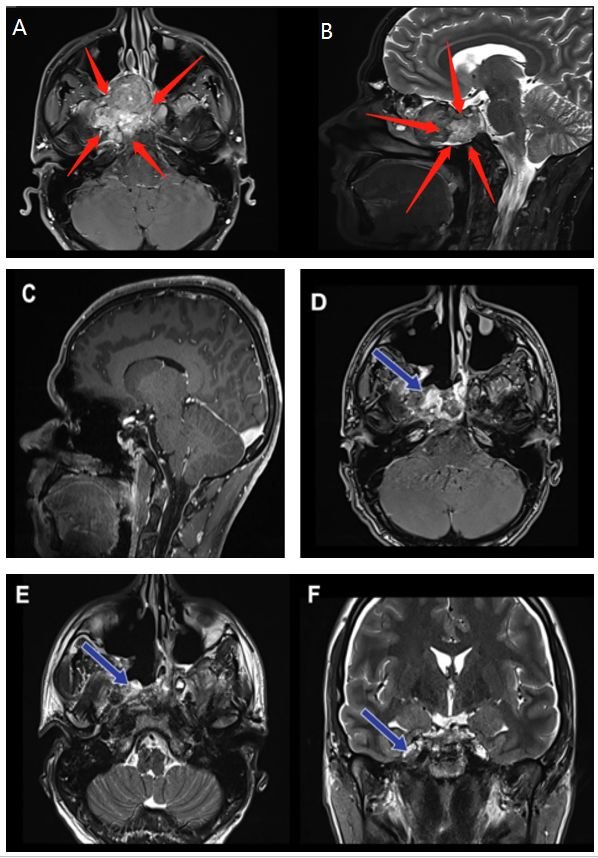

术前(红色箭头):A、B图显示位于右海绵窦中心的脊索瘤病变。病变集中在右侧海绵窦和翼骨上,并在右侧邻卵圆孔。

手术过程:神经内镜单鼻孔经蝶窦手术切除

术后(蓝色箭头):C图表示矢状位显示无肿瘤残余。D、E、F图显示轴位、冠状位脊索瘤被绝大部分切除。